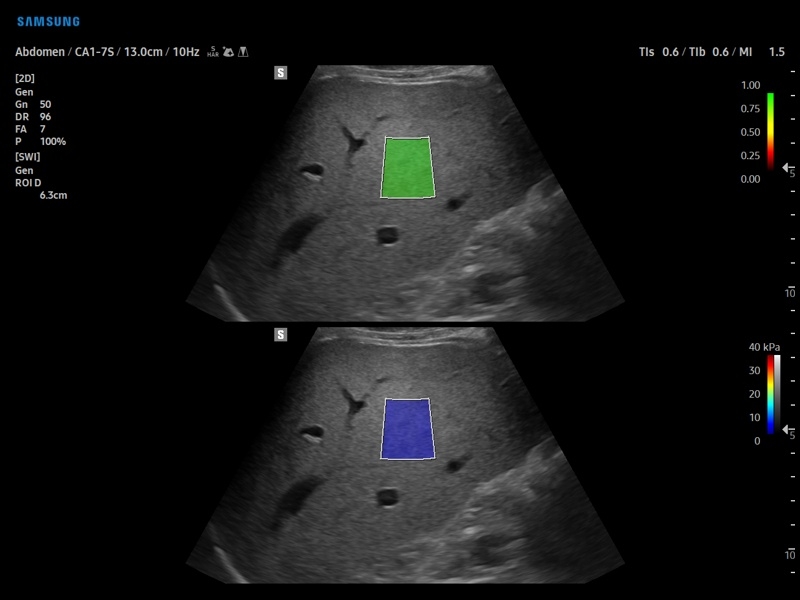

• S-Shearwave Imaging для эластографии сдвиговой волной

Компрессионная, Сдвиговая

Эластография сдвиговой волной/Эластометрия:

Да

S-Shearwave imaging:

• Модуль S-Shearwave imaging – программа цветовой сдвиговой эластографии позволяющая автоматически определять индекс жесткости различных участков исследуемого объекта в кПа или м/с, получая при это еще и индекс достоверности данных RMI.